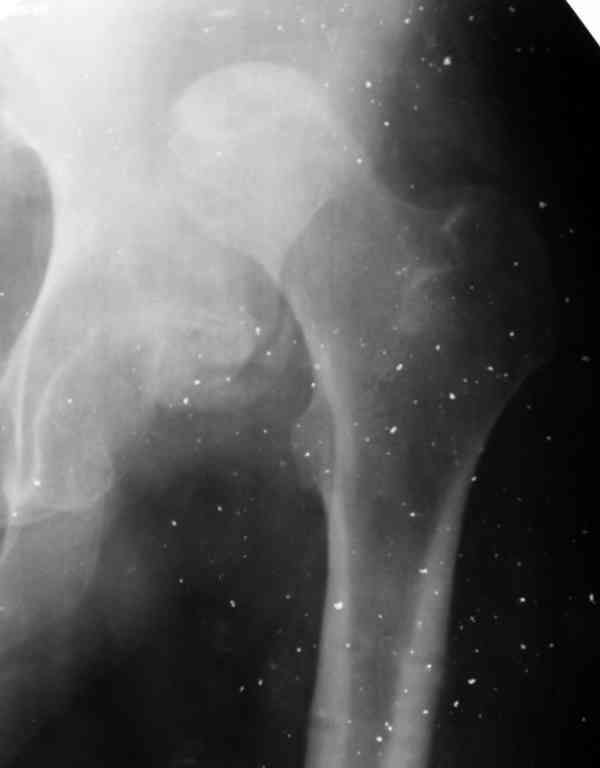

Moghno i tak kak sdelali my: pelvic support + tibial and equinus correction .

Слайд 1

Слайд 2

Слайд 3

Слайд 4

Devushka predstavlennaya na snimke nachala s LLD 9 cm, valgus deformation of the tibia, huge Trendelenburg( vidno na snimke).

Seichas : no LLD ,no Trendelenburg, reasonable hip motion.A samoe glavnoe ei ne predstoit kaghdye 10-15 let delat revision THR.